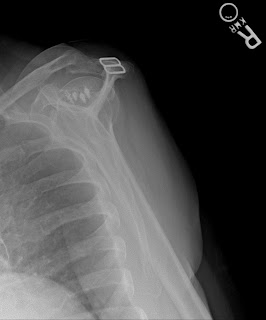

The x-rays below are from a different patient but the operation was by the same surgeon. In this patient, there is moderate pain because the anchors remain in the bone. The repair has failed. If you look carefully, you can see that the head of the humerus (the bone with the metal anchors) has moved upwards and now is touching the bone above it (the acromion). This can only happen when there is a massive rotator cuff tear. Once again, no MRI needed. This patient cannot lift her arm at all and has what we call a pseudoparalyitc shoulder.

This patient is considering a reverse should arthroplasy. She is the same age as the first patient but much more active. I suspect she would do well with the new shoulder.